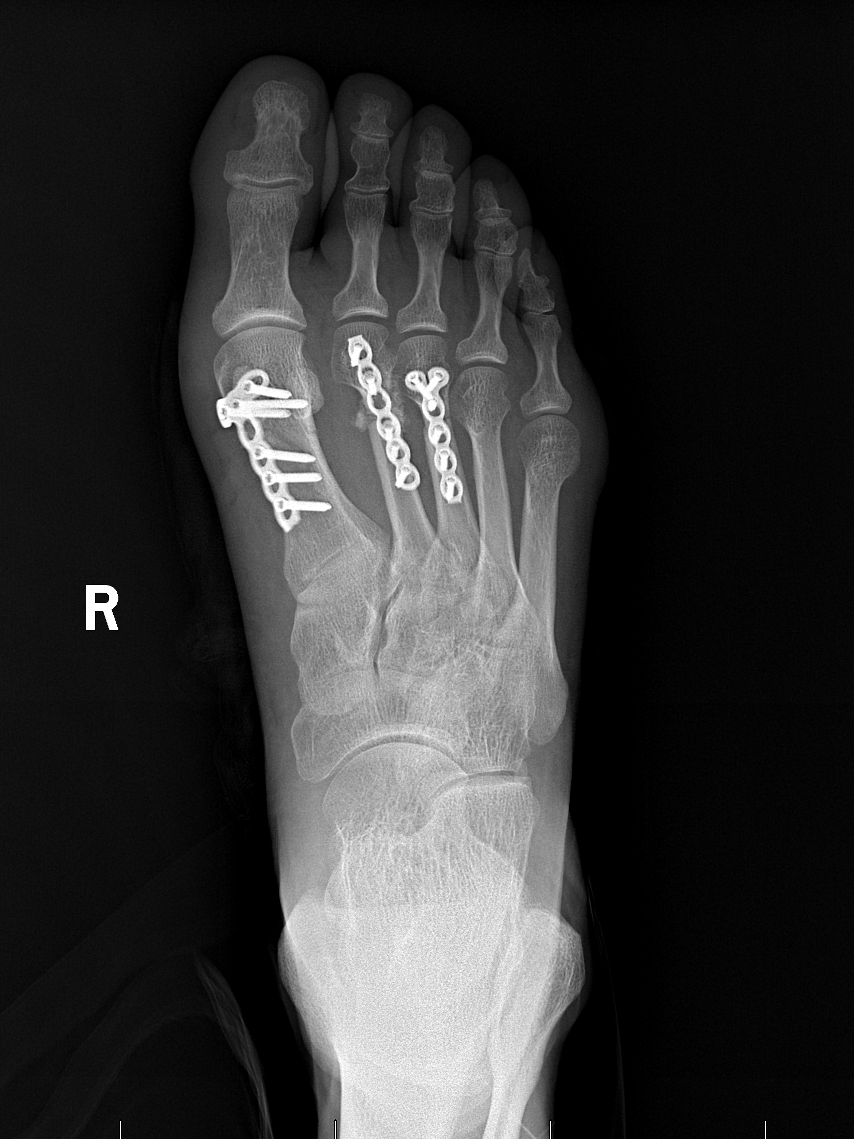

2025年4月18日,李先生因意外受伤来到玉溪市中山医院骨科就诊。经详细检查会诊,李先生被诊断为右侧开放性多发性足骨折、右足第1、2、3跖骨骨折。骨科团队迅速为李先生制定了个性化治疗方案,并于4月28日,由骨科副主任医师曾润华主刀,成功实施“跖骨骨折切开复位钢板内固定术”。手术后,医护人员每日密切关注李先生的病情,耐心指导他进行康复训练。在医护团队的精心照料下,李先生恢复良好,疼痛明显减轻,患部功能逐步恢复,于5月18日顺利出院。为表达感谢,李先生特意送来一面印有“医德高尚医术精,关爱病患暖人心”的锦旗,向曾润华医生及医护人员表达诚挚谢意。

患者术后X线影像